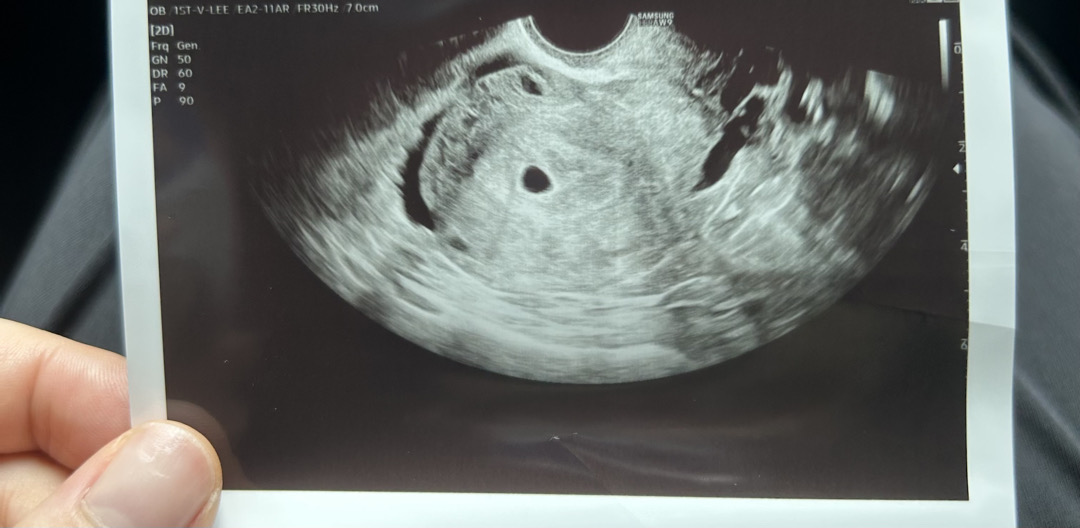

5주0일차 아기집 보고왔어요♥

둘째인데도 초음파 보니 또 새롭네요 ㅎㅎㅎ